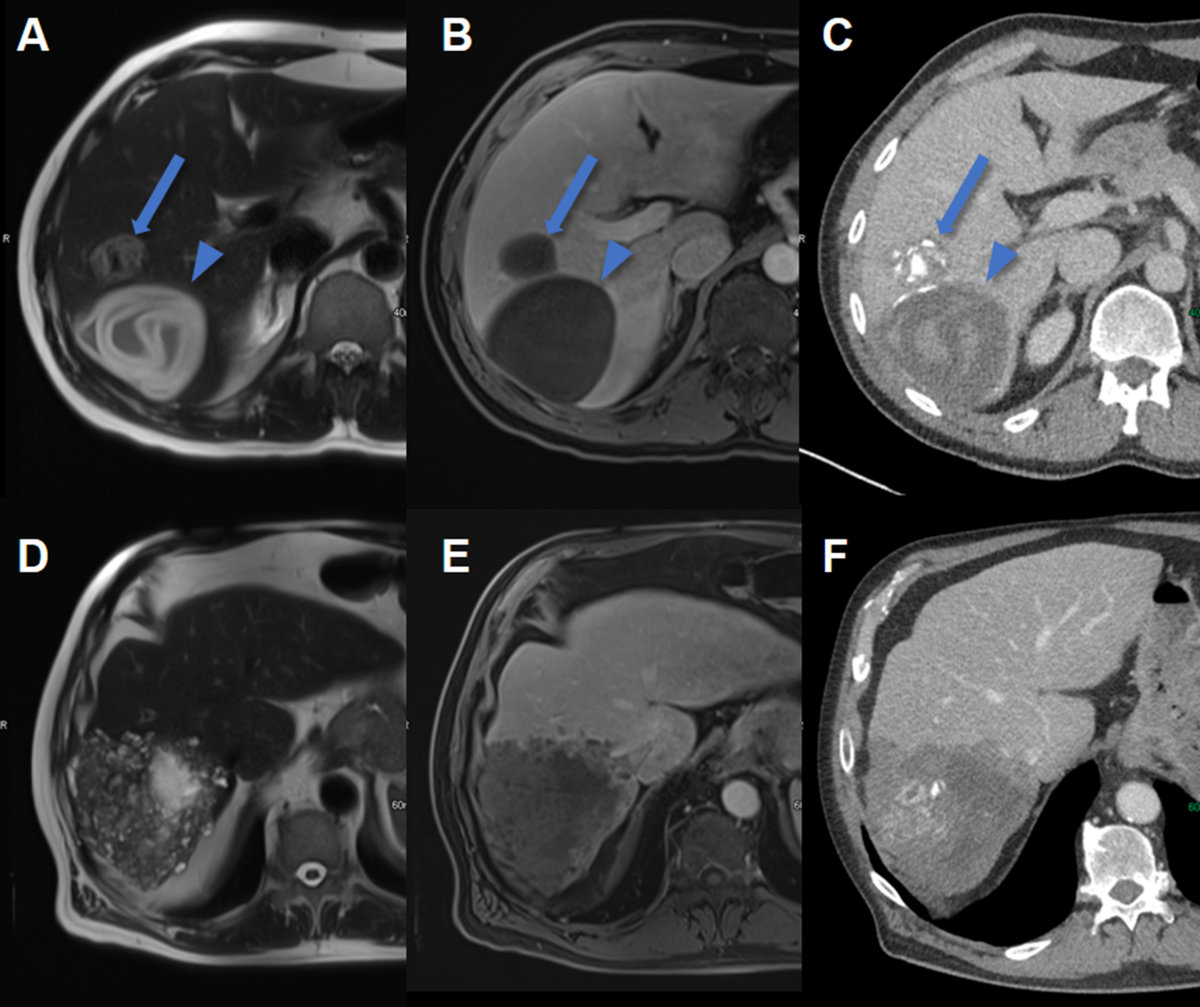

The WHO-IWGE classification for cystic echinococcosis can be applied for CT and MRI, with MRI being superior to CT in reproducing the conventional ultrasound-stages of cystic echinococcosis, and CT being superior to conventional ultrasound and MRI in demonstrating minute calcifications [33]. Cystic echinococcosis fluid on CT demonstrates fluid attenuation (approximately 0 HU). Calcifications are seen as hyperdensities, with faint calcifications potentially being missed after the administration of an intravenous contrast agent, which is the reason why unenhanced images should be acquired. On MRI, theses cysts are hyperintense on T2w images, and daughter cysts or membranes are more easily visible than on CT (figure 9).

Figure 9Hepatic echinococcosis on CT and MRI. A T2w axial MRI, B T1w fs axial image after gadolinium based i.v. contrast and C CT image after iodine based i.v. contrast in a 37-year-old male patient with cystic echinococcosis (E. granulosus) demonstrating two lesions: the anterior with heterogenous signal on T2w, lack of enhancement and coarse calcifications visualized on CT (arrow, CE5). The posterior lesion with hyperintense detached membrane on T2w, lack of enhancement and faint visibility of the membrane on CT (arrowhead, CE3). D T2w axial MRI, E T1w fs axial image after gadolinium based i.v. contrast and F CT image after iodine based i.v. contrast in a 74-year-old male patient with alveolar echinococcosis (E. mulitlocularis) with pathognomonic microcystic features on T2w image and partial necrosis, infiltrative aspect and coarse calcifications seen on CT.

MRI is also the second imaging modality of choice for alveolar echinococcosis after conventional ultrasound. On MRI, microcystic, alveolar structures are a pathognomonic feature of alveolar echinococcosis (figure 9). However, many lesions are atypical and of an infiltrative character. For detection of calcifications and in patients incompatible with MRI, CT usually has a role. On CT images, alveolar echinococcosis presents as mixed hyperdense-hypodense lesions with possible necroses.